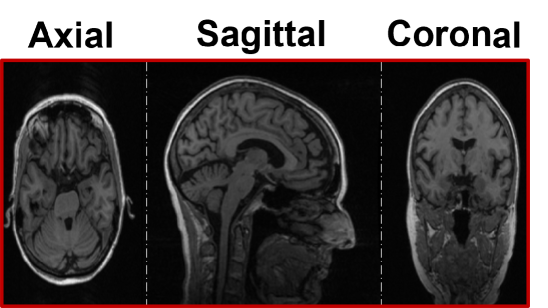

Figure 4: The MRI preprocessing pipeline depicted across three orthogonal views of 3D MRI images.

Data Preprocessing. Preprocessing is imperative in medical imaging registration, as discussed in Section III-A. Our MRI image preprocessing pipeline, illustrated in Fig. 4, consists of three essential steps: